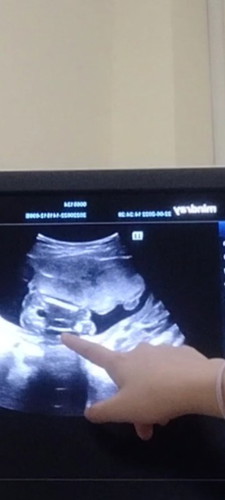

เพศไหนคะ หญิงหรือชาย

แม่ๆว่าเพศไหนคะ หมอบอกว่า อาจจะผ.ญ อาจจะ แต่ไม่100% 😂

เหมือนผญ.นะแม่